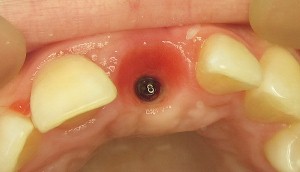

8ヶ月後にインプラントを入れるために戻ってきました。1時間で済む簡単な治療で、仮歯は歯茎を形作るために使われました。Daniele 先生は長時間の治療だったにもかかわらず無償で行ってくれました。

医師は歯茎がきちんと形作られているか確認することに重点を置いて、よりよい治療結果を得るために大事な要素だと理解しました。